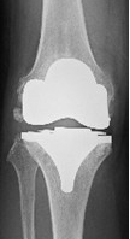

人工膝関節

置換術(MA法)MA TKA

置換術(KA法)KA TKA